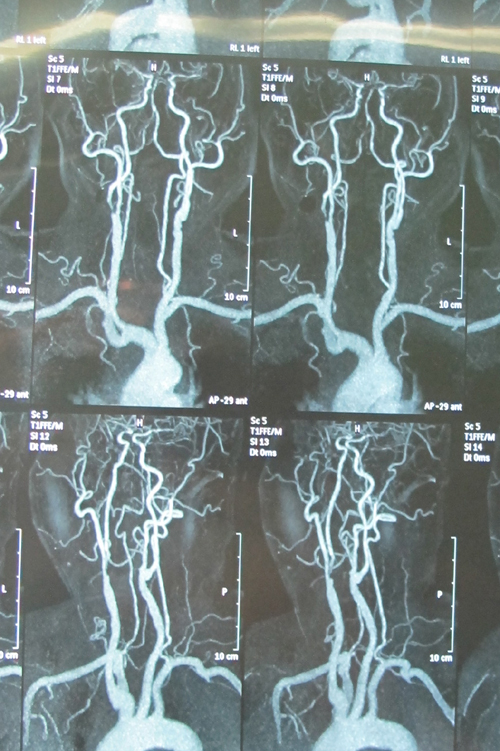

CEMRA:1、两侧颈总、颈内、颈外动脉,两侧椎动脉、基地动脉及右侧锁骨下动脉粥样硬化2、左侧颈总动脉、右侧颈内动脉、左侧颈外动脉、右椎动脉、右侧锁骨下动脉局限性、阶段性狭窄。